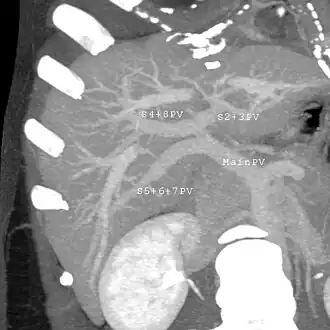

Couinaud classification system

In the widely used Couinaud system, the functional lobes are further divided into a total of eight subsegments based on a transverse plane through the bifurcation of the main portal vein.[30] The caudate lobe is a separate structure that receives blood flow from both the right- and left-sided vascular branches.[31][32] The Couinaud classification divides the liver into eight functionally independent liver segments. Each segment has its own vascular inflow, outflow and biliary drainage. In the centre of each segment are branches of the portal vein, hepatic artery, and bile duct. In the periphery of each segment is vascular outflow through the hepatic veins.[33] The classification system uses the vascular supply in the liver to separate the functional units (numbered I to VIII) with unit 1, the caudate lobe, receiving its supply from both the right and the left branches of the portal vein. It contains one or more hepatic veins which drain directly into the inferior vena cava.[30] The remainder of the units (II to VIII) are numbered in a clockwise fashion:[33]

With the recent advances of noninvasive imaging, living liver donors usually have to undergo imaging examinations for liver anatomy to decide if the anatomy is feasible for donation. The evaluation is usually performed by multidetector row computed tomography (MDCT) and magnetic resonance imaging (MRI). MDCT is good in vascular anatomy and volumetry. MRI is used for biliary tree anatomy. Donors with very unusual vascular anatomy, which makes them unsuitable for donation, could be screened out to avoid unnecessary operations.

MDCT image. 3D image created by MDCT can clearly visualize the liver, measure the liver volume, and plan the dissection plane to facilitate the liver transplantation procedure. -